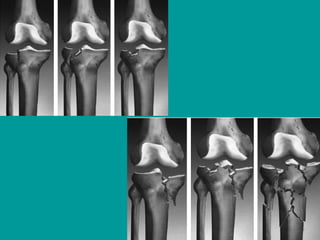

Classification

Imaging

• AP, lateral, and oblique views are usually

adequate for demonstrating these

fractures .

• Computed tomography (CT) scanning .

• Magnetic resonance imaging (MRI),